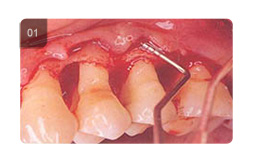

|              接受傳統手術治療後  |         ||||

|              治療前  |                          治療後  |             |||